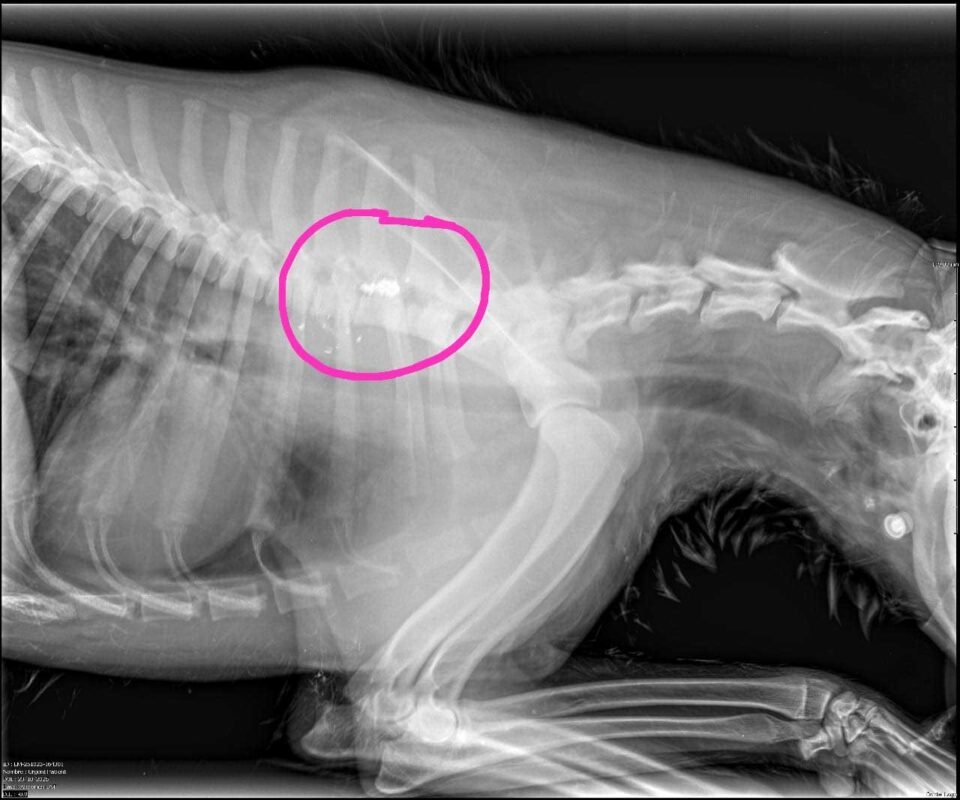

“Tiene una bala alojada en la columna”

En diálogo con Jornada Radio, Marcelo Luzio relató que el animal fue hallado “a la altura de Finca La Preferida, cerca de donde se vio al puma”, y que tras los primeros estudios confirmaron una grave lesión:

“El perrito tiene una bala alojada en la columna. Por eso no puede mover las patas traseras”, explicó Luzio.